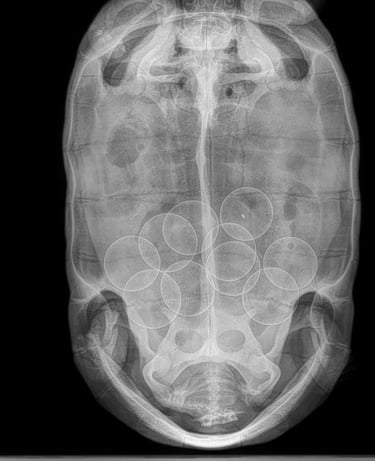

Most of the time the females come to us with EGGS inside of them!

X-rays (when recommended) to detect retained eggs, ingested rocks, or internal issues